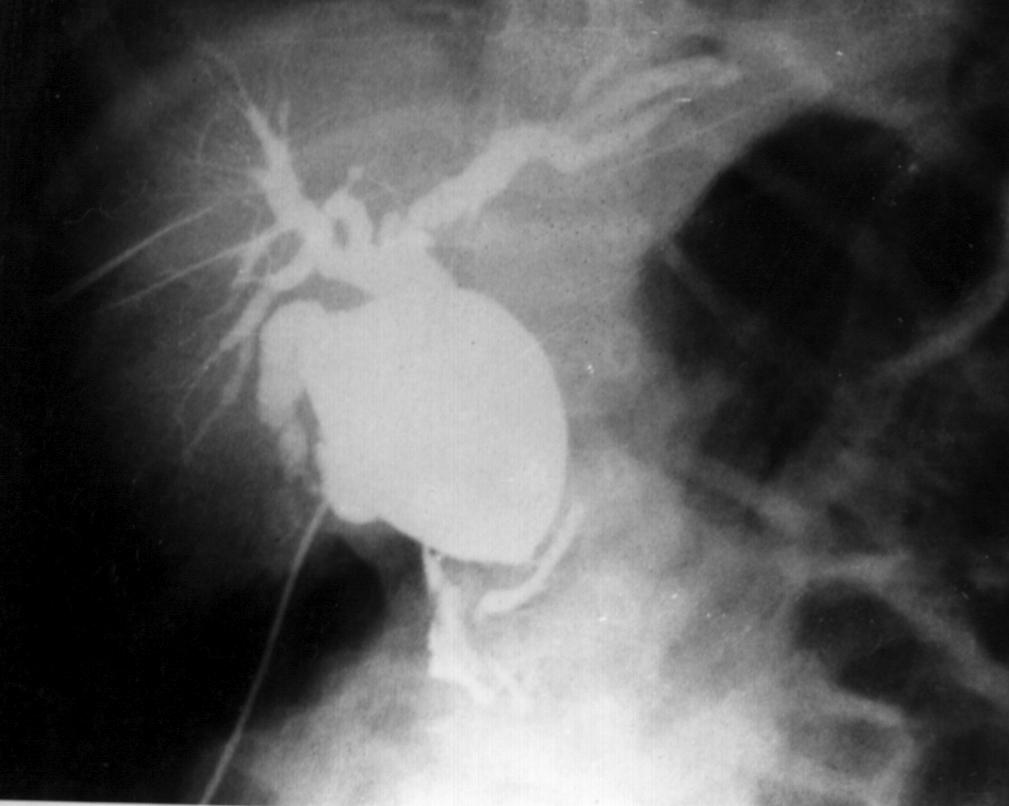

Cbd1.jpg (53776 bytes)